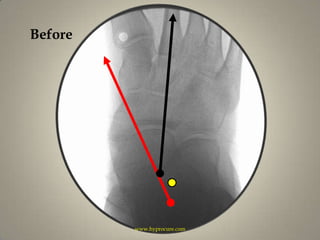

Beforewww.hyprocure.com

HyProCured™www.hyprocure.com